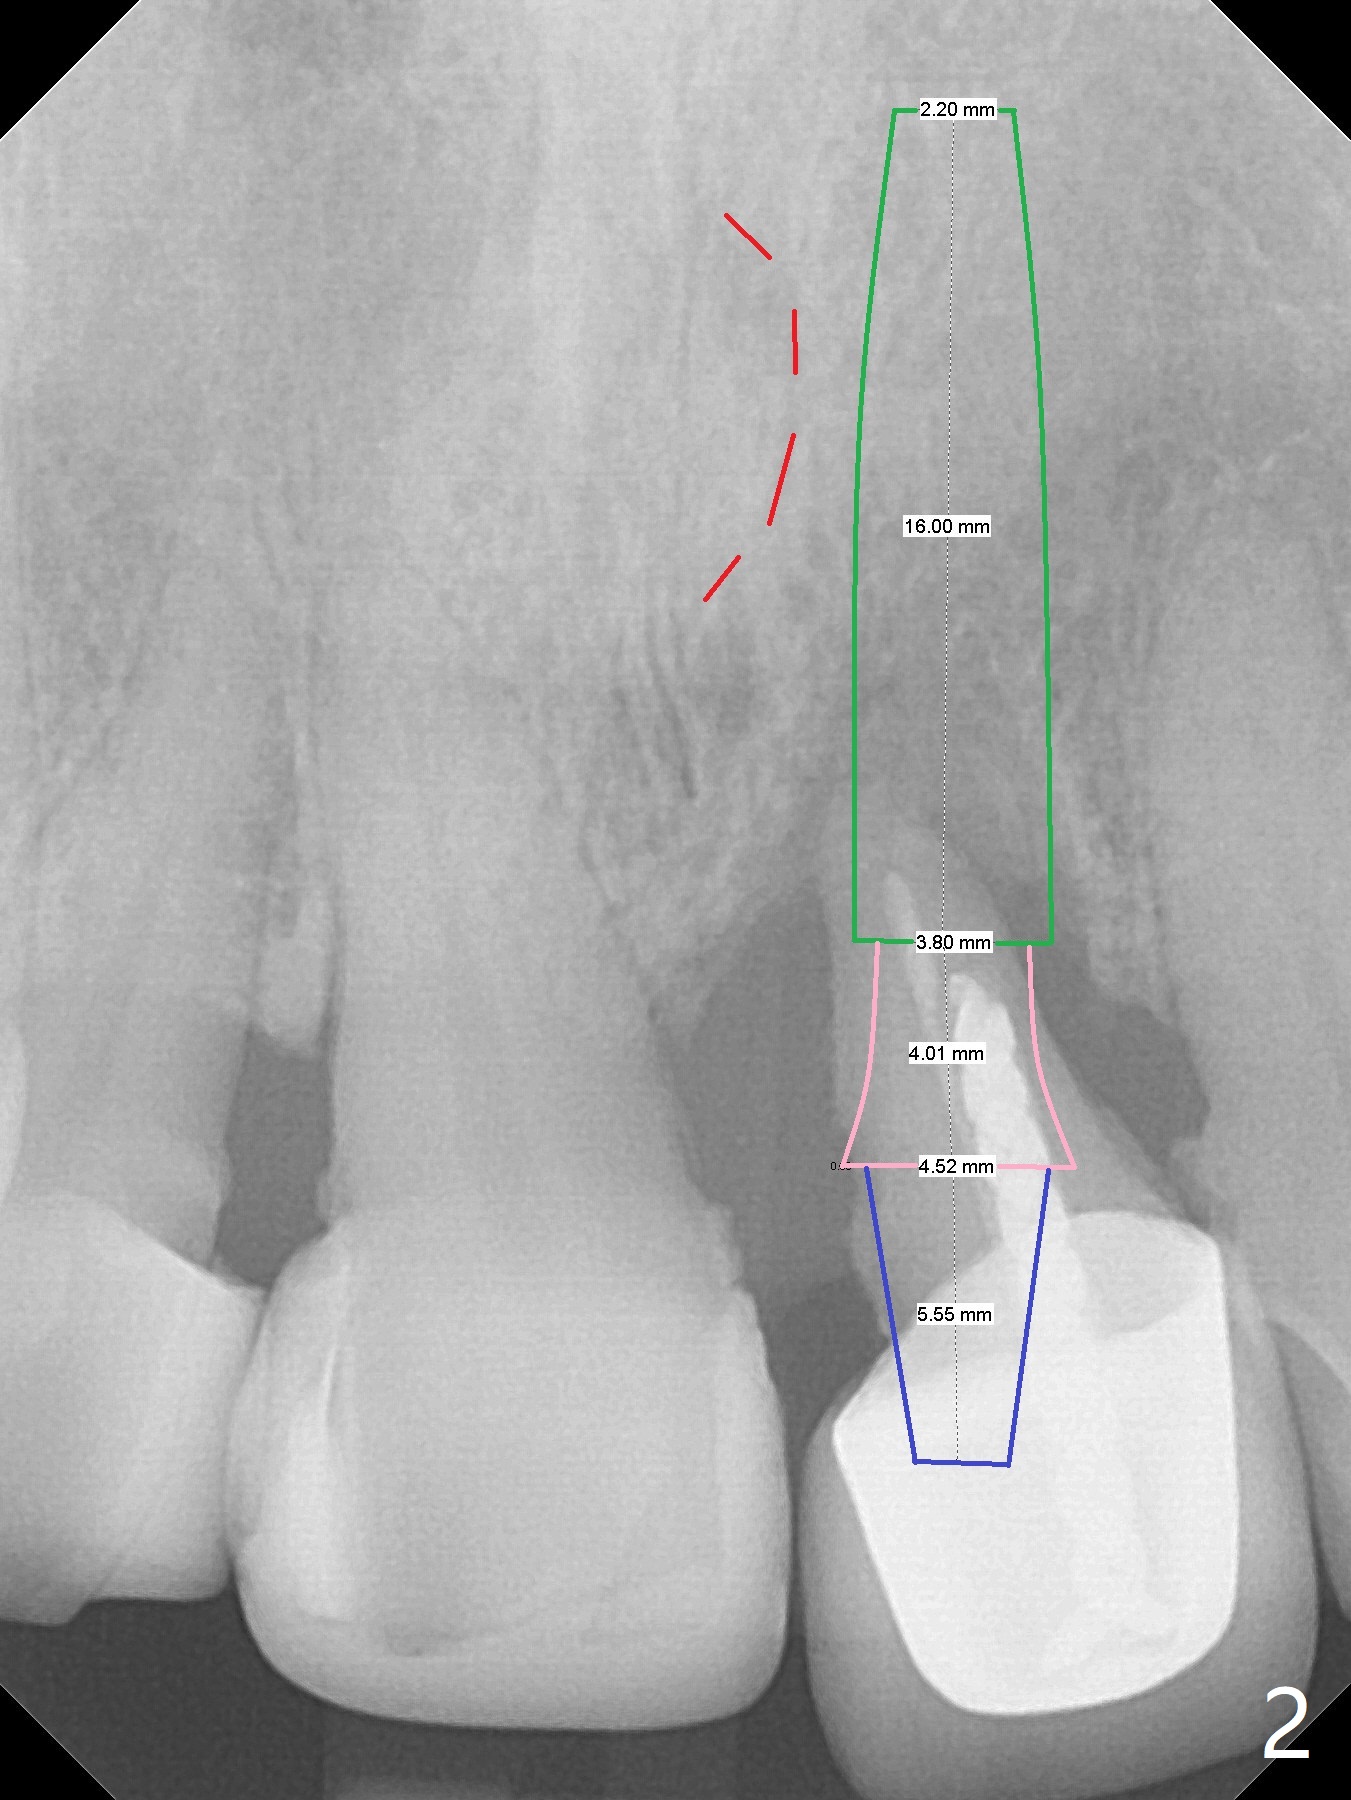

Concern of a 48-year-old woman is the exfoliating central incisor (Fig.1). After SRP (Fig.3,4), a long implant will be placed for stability (Fig.2), considering a posterior missing tooth (Fig.4).